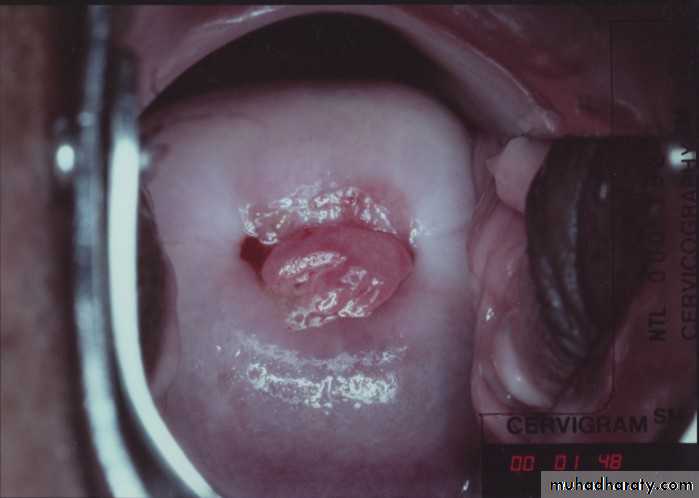

Cervical ectropion

Is the presence of everted endocervical columnar epithelium on the ectocervix.it is in reality an area of columnar epithelium that has not yet undergone squamous metaplasia. it occurs when the cervix grows rapidly and enlarges under the influence of estrogen, after menarche and during pregnancy. And also seen in women under the influence of estrogen (combined oral contraceptive pills COCP, pregnancy).

it is a normal, physiological occurrence in a woman’s life.

it is previously called Cervical erosion which is very inappropriate name and best to be avoid as it conveys quite the wrong impression of what is really a normal phenomenon.

Speculum examination:*Bright red area is seen around the external os continuous with the endocervix with clearly defined outer edge. The eversion of the columnar epithelium is more pronounced on the anterior and posterior lips of the ectocervix and less on the lateral lips.

*It is not tender.

*It bleeds from multiple pinpoint areas when touched.